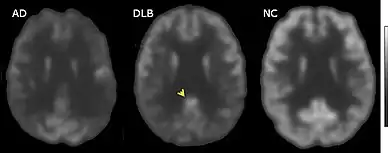

Direct laboratory-measurable biomarkers for DLB diagnosis are not known, but several indirect methods can lend further evidence for diagnosis.[25] The indicative diagnostic biomarkers are: reduced dopamine transporter uptake in the basal ganglia shown on PET or SPECT imaging; low uptake of 123iodine-metaiodobenzylguanidine (123I-MIBG) shown on myocardial scintigraphy; and loss of atonia during REM sleep evidenced on polysomnography. Supportive diagnostic biomarkers (from PET, SPECT, CT, or MRI brain imaging studies or EEG monitoring[124]) are: lack of damage to medial temporal lobe (damage is more likely in AD[116]); reduced occipital activity; and prominent slow-wave activity on EEG.[25]

If DLB is suspected when parkinsonism and dementia are the only presenting features, PET or SPECT imaging may show reduced dopamine transporter activity. A DLB diagnosis may be warranted if other conditions with reduced dopamine transporter uptake can be ruled out.[25]

PET or SPECT imaging can be used to detect reduced dopamine transporter uptake and distinguish AD from DLB.[57][149] Severe atrophy of the hippocampus is more typical of AD than DLB.[150] Before dementia develops (during the mild cognitive impairment phase), MRI scans show normal hippocampal volume. After dementia develops, MRI shows more atrophy among individuals with AD, and a slower reduction in volume over time among people with DLB than those with AD.[33] Compared to people with AD, FDG-PET brain scans in people with DLB often show a cingulate island sign.[33]